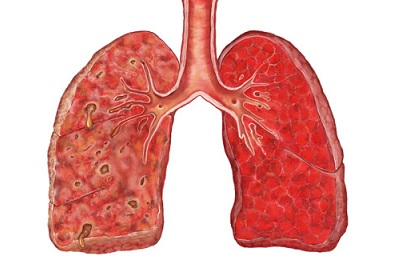

Внутрибольничная пневмония – это легочная инфекция, развившаяся спустя двое и более суток после поступления больного в стационар, при отсутствии признаков заболевания на момент госпитализации. Проявления внутрибольничной пневмонии аналогичны таковым при других формах воспаления легких: лихорадка, кашель с мокротой, тахипноэ, лейкоцитоз, инфильтративные изменения в легких и т. п., однако могут быть слабо выраженными, стертыми. Диагноз основывается на клинических, физикальных, рентгенологических и лабораторных критериях. Лечение внутрибольничной пневмонии включает адекватную антибиотикотерапию, санацию дыхательных путей (лаваж, ингаляции, физиометоды), инфузионную терапию.

Внутрибольничная пневмония клинически отличается тяжелым течением. Диагноз госпитальной пневмонии устанавливается на основании легочных и внелегочных проявлений, которые являются признаками поражения легких и интоксикации организма:

Легочные проявления: кашель, мокрота (отсутствие или обильное выделение гнойной мокроты), боли в грудной клетке, выраженная одышка, учащенное и поверхностное дыхание.

Присутствуют физикальные признаки, такие как: укорочение (притупление) перкуторного звука, бронхиальное дыхание, влажные хрипы, крепитация при прослушивании фонендоскопом области воспаления, шум трения плевры, выделение большого количества мокроты с большим количеством гноя.